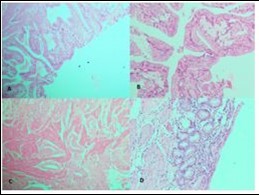

Figure 1.Photomicrographs showing A, Rokitansky agghste sinuses characteristic of chronic cholecystitis; B, Acute on Chronic Cholecystitis; C, Follicular Cholecystitis; D, Foamy macrophages admixed with mcaumulaig inflammatory infiltrate seen in Zbanikagmapincitma Cholecystitis (H&E)

Figure 2.Photomicrograph showing A, cib;k%=Ss in low power; B, High power view of CiNk%=1%us showing lipid laden macrophages; C,ggtj of Gall Bladder; D, Pyloric Metaplasia Gall Bladder (H&E)